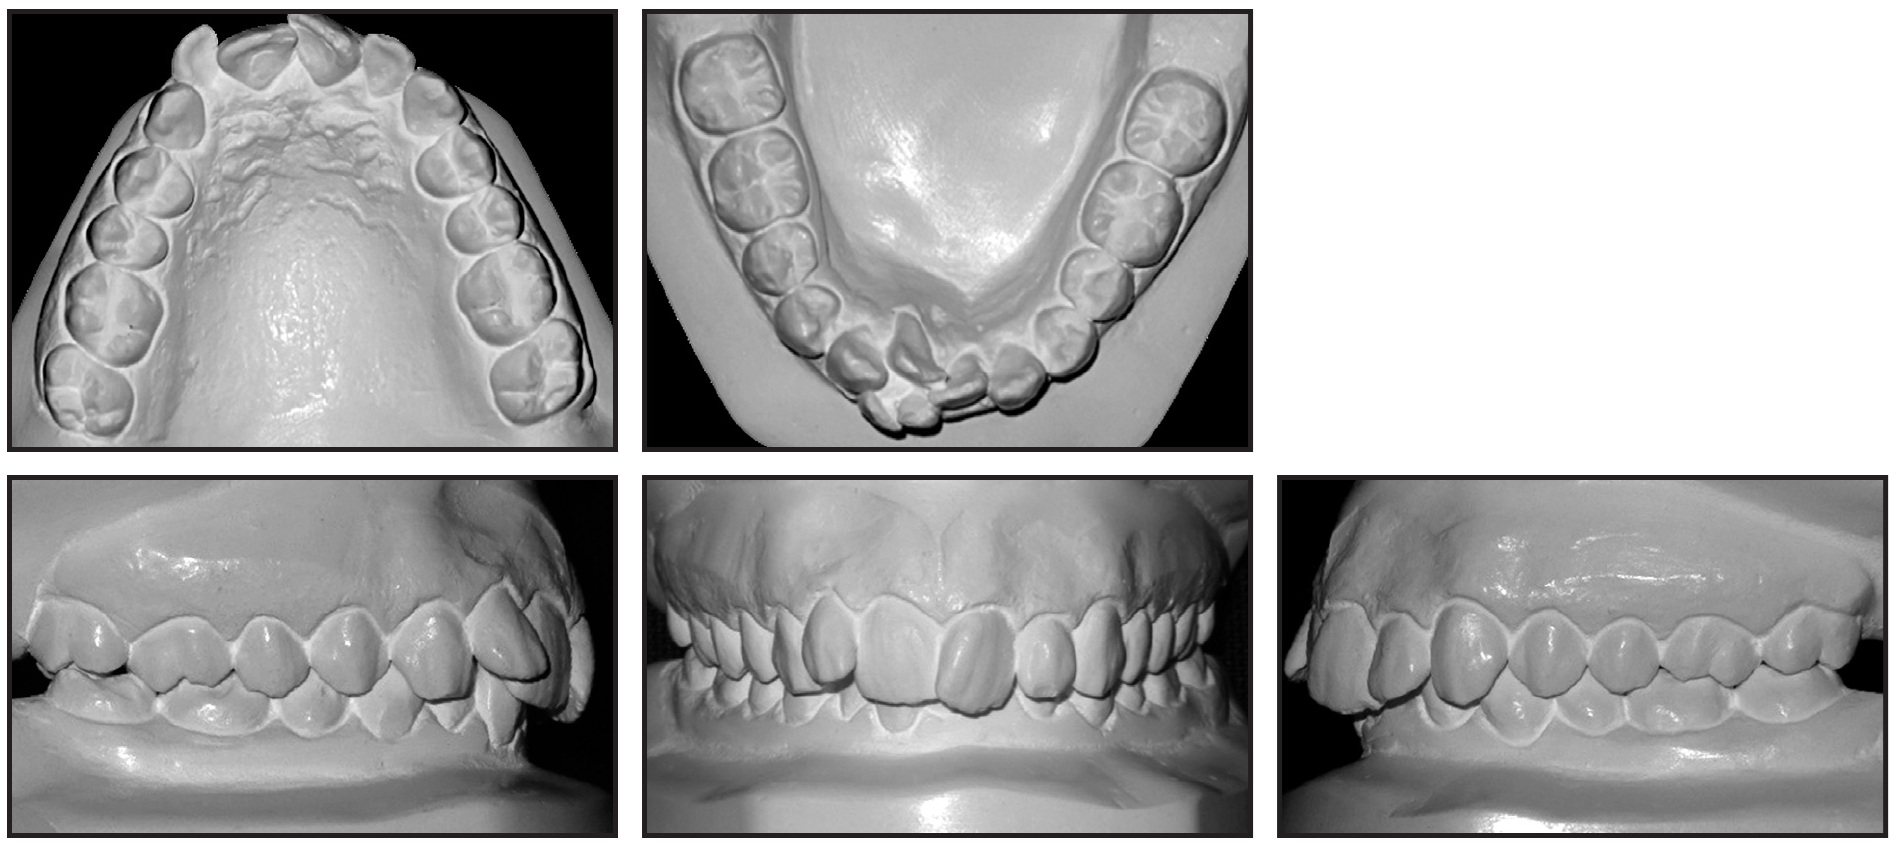

Total treatment time was 35 months (Fig. 5). The balanced profile and Class I canine and molar relationships were successfully maintained, and the patient was highly satisfied with his teeth and profile. The mandibular incisors were aligned, with the proper torque. The skeletal maxillomandibular relationship was slightly improved, the maxillary incisors were slightly proclined, and the mandibular incisors were uprighted (Table 1). The overjet and overbite were reduced, and the upper and lower lip positions and nasolabial angle were basically unchanged.

Fig. 5 Patient after 35 months of treatment (records taken seven months later).